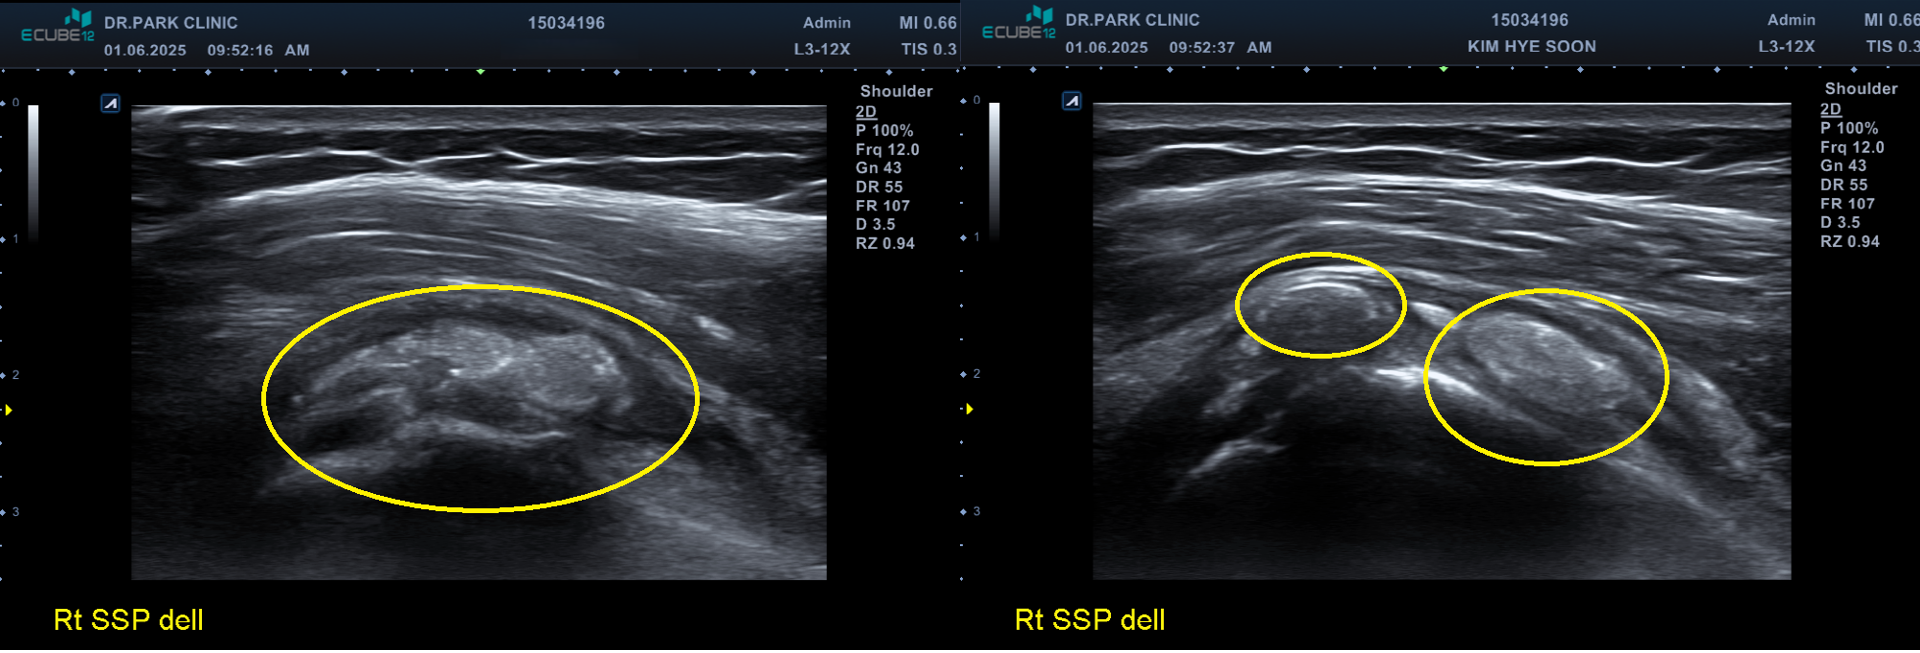

이분은 극심한 통증으로 아침 진료 시작시간 30분전부터 와서 기다리고 있는 분입니다. 내원 3일전부터 약간씩 아프다 내원 전날 밤에 통증이 극심해져서 밤새 잠도 못자고 병원에 오셨습니다. 통증이 워낙 심해서 옷을 입고 벗는것도 스스로 불가능했고 초음파검사기를 가져다 대는것도 아파하는 정도였습니다.

초음파 검사에서 보면 어깨에 아주 커다란 석회가 있고 주변으로 염증이 심한 상태였습니다.

처음에는 염증을 가라앉히는 주사, 먹는약, 물리치료로 통증을 가라앉히고 그 다음부터 5회의 석회흡입술과 체외충격파 치료를 했습니다.

위의 비포 & 애프터 사진을 보면 알 수 있지만 5회의 석회 흡입술과 체외충격파 치료로 아주 커다란 석회가 드라마틱하게 사라진걸 볼 수 있습니다. 이 환자분의 경우 염증 주사를 맞고 이틀만에 통증은 거의다 사라졌고 커다란 석회마저 완전히 제거되어 치료 만족도가 매우 높은 분이었습니다.